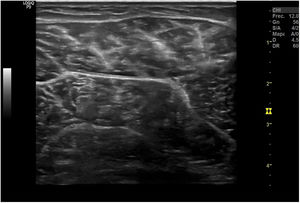

Técnica de exploraciónLa exploración ecográfica se realiza con sonda lineal de alta frecuencia (7,5-12MHz). Se debe hacer de forma estandarizada en las distintas áreas anatómicas, que permita identificar los diferentes tejidos, tanto normales como patológicos, observados en reposo y en movimiento. Los signos ecográficos patológicos habituales son la colección hipo- o anecoica comprimible y desplazable en recesos articulares en los derrames (fig. 10), el engrosamiento hipo- o anecoico del tejido en una vaina sinovial con o sin líquido en la tenosinovitis (fig. 11), la interrupción y espiculación de la línea cortical en las erosiones óseas (fig. 12), la aparición de material ecogénico en el espacio sinovial o articular en las sinovitis y el pannus respectivamente, y la presencia de señal doppler en los procesos con inflamación activa (fig. 13). Deben identificarse en 2 planos distintos para evitar la confusión por la presencia habitual de artefactos. Se ha de aplicar gel suficiente que permita el contacto de toda la superficie de la sonda con la piel, evitando el aire entre ambos, y se debe ejercer una presión firme pero no excesiva, que impida colapsar los neovasos visibles mediante el doppler. Estos serán más fáciles de encontrar con la articulación en flexoextensión fisiológica.

La ecografía permite detectar sinovitis y erosiones de forma mucho más precoz que la radiografía convencional (RX), por lo que es útil para el diagnostico y seguimiento. Su inmediatez y disponibilidad la hacen más aplicable que la RM. Además, detecta inflamación con mayor sensibilidad que la exploración física (EF) y permite distinguir entre derrame y sinovitis en escala de grises27. Con la técnica de power-doppler permite localizar neovascularización sinovial relacionada con actividad inflamatoria, siendo la sinovitis el mejor predictor de erosión radiográfica28,29.Esto la hace especialmente eficaz para el diagnóstico en fases iniciales de la artritis cuando la EF no puede aclarar aún la existencia de signos inflamatorios articulares, si bien sus hallazgos no son específicos de artritis reumatoide. También permite valorar la extensión de la artritis, mediante la exploración ampliada de las articulaciones de manos, muñecas y metatarsofalángicas, permitiendo detectar inflamación en articulaciones aún asintomáticas30,31. Hay datos sólidos que demuestran la capacidad de la ecografía para la detección más precoz de erosiones que la RX32,33, aunque su capacidad es inferior a la de la RM33–35.